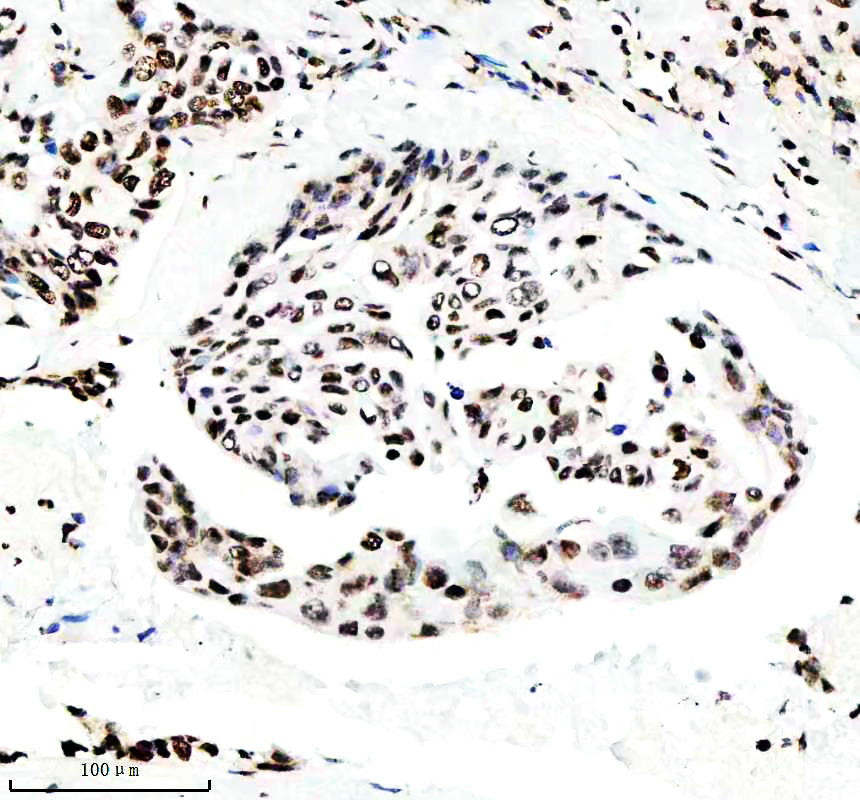

IHC analysis of Histone H3 (acetyl K14) using anti-Histone H3 (acetyl K14) antibody (BM4151) .

Histone H3 (acetyl K14) was detected in a paraffin-embedded section of human clear cell renal cell carcinoma tissue. The tissue section was incubated with rabbit anti-Histone H3 (acetyl K14) Antibody (BM4151) at a dilution of 1:200 and developed using HRP Conjugated Rabbit IgG Super Vision Assay Kit (Catalog # SV0002) with DAB (Catalog # AR1027) as the chromogen.